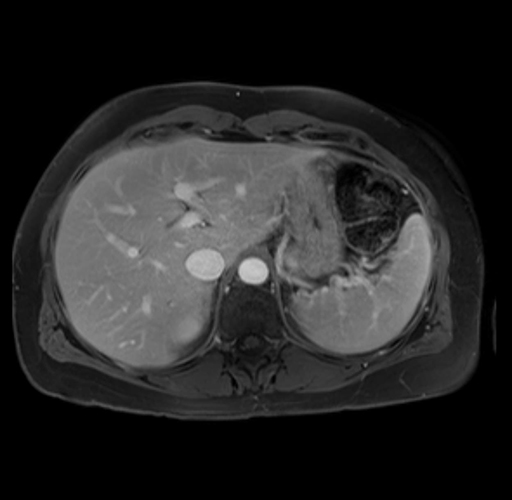

Imaging Analysis

Look through the patient's CT scan to identify any areas of concern for the necessary procedure.

Based on your CT findings, which issue(s) are present and would give reason for "planned slowing down moment(s)" in this case?